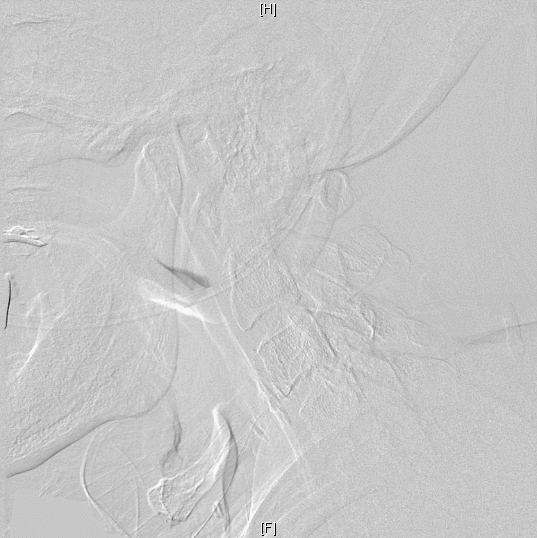

经血管评估检查确认,陈伯的彩超显示其左颈内动脉起始段狭窄达90%,血流速度>300cm/s(正常值<100cm/s),且 DSA证实左侧颈内动脉极重度狭窄(接近闭塞),仅依靠微弱的侧支循环维持脑部供血。“虽然血管尚未完全闭塞,但残余血流已无法满足正常生理需求。更危险的是,斑块表面的血栓或粥样硬化成分碎屑被血流冲至颅内,恰好堵塞左侧大脑语言中枢的供血动脉,最终引发急性脑梗死。”郑峥说。

“经过脑血管造影证实后,我们立即着手为患者设计左侧颈内动脉支架植入术方案。这是一种通过右侧股动脉入路的微创介入手术,旨在开通狭窄血管、恢复脑部供血。”

据了解,在局部麻醉下成功为患者实施了支架成形手术,术中术后陈伯也没有出现明显不适反应,神经功能查体时,除了陈伯入院前存在的言语功能障碍、右侧肢体乏力外,无新发的神经功能缺损,且复查CT后也并没有发现新发的梗死病灶及出血的病灶,已顺利出院。

术前(上)、术后(下)影像对比